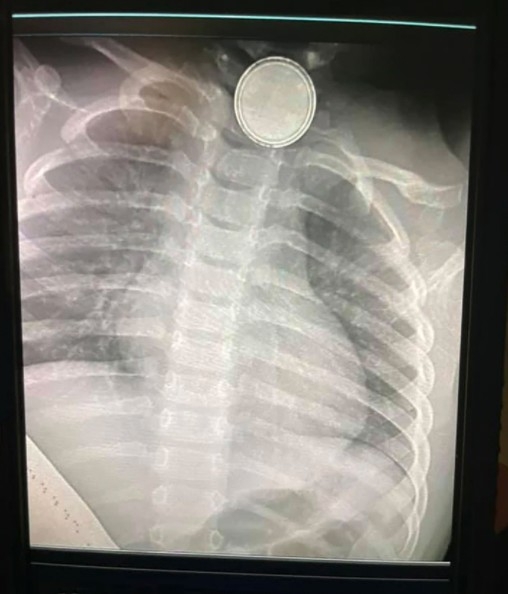

惟至翌日,Trista 卻無意發現家中的電視遙控器內的一顆鈕扣型電池(水銀電池)不見了,因擔心女兒誤服了電池,故便隨即再次帶女兒求至急症室求診。經過X光檢查後發現,真的有一顆鈕扣型電池卡在了女兒食道內。而醫生見狀亦立刻用內視鏡取出電池。